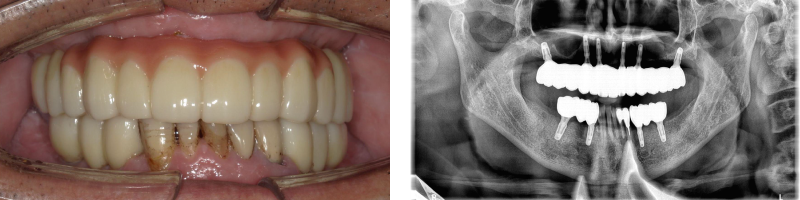

インプラント症例

治療内容 60代男性 抜歯しインプラント埋入

期間 抜歯+インプラント埋入+仮歯装着まで1回、3か月後最終被せ物装着

費用 2,690,000円

(インプラント5本+被せ物12本)

注意点/副作用 外科処置が必要・全身状態によりできない場合がある。